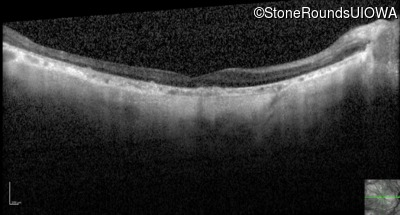

Optical Coherence Tomography - Right - 10/200 sc

Exemplar / OCT Stack

OCT Stack

Optical Coherence Tomography - Left - 10/160 sc